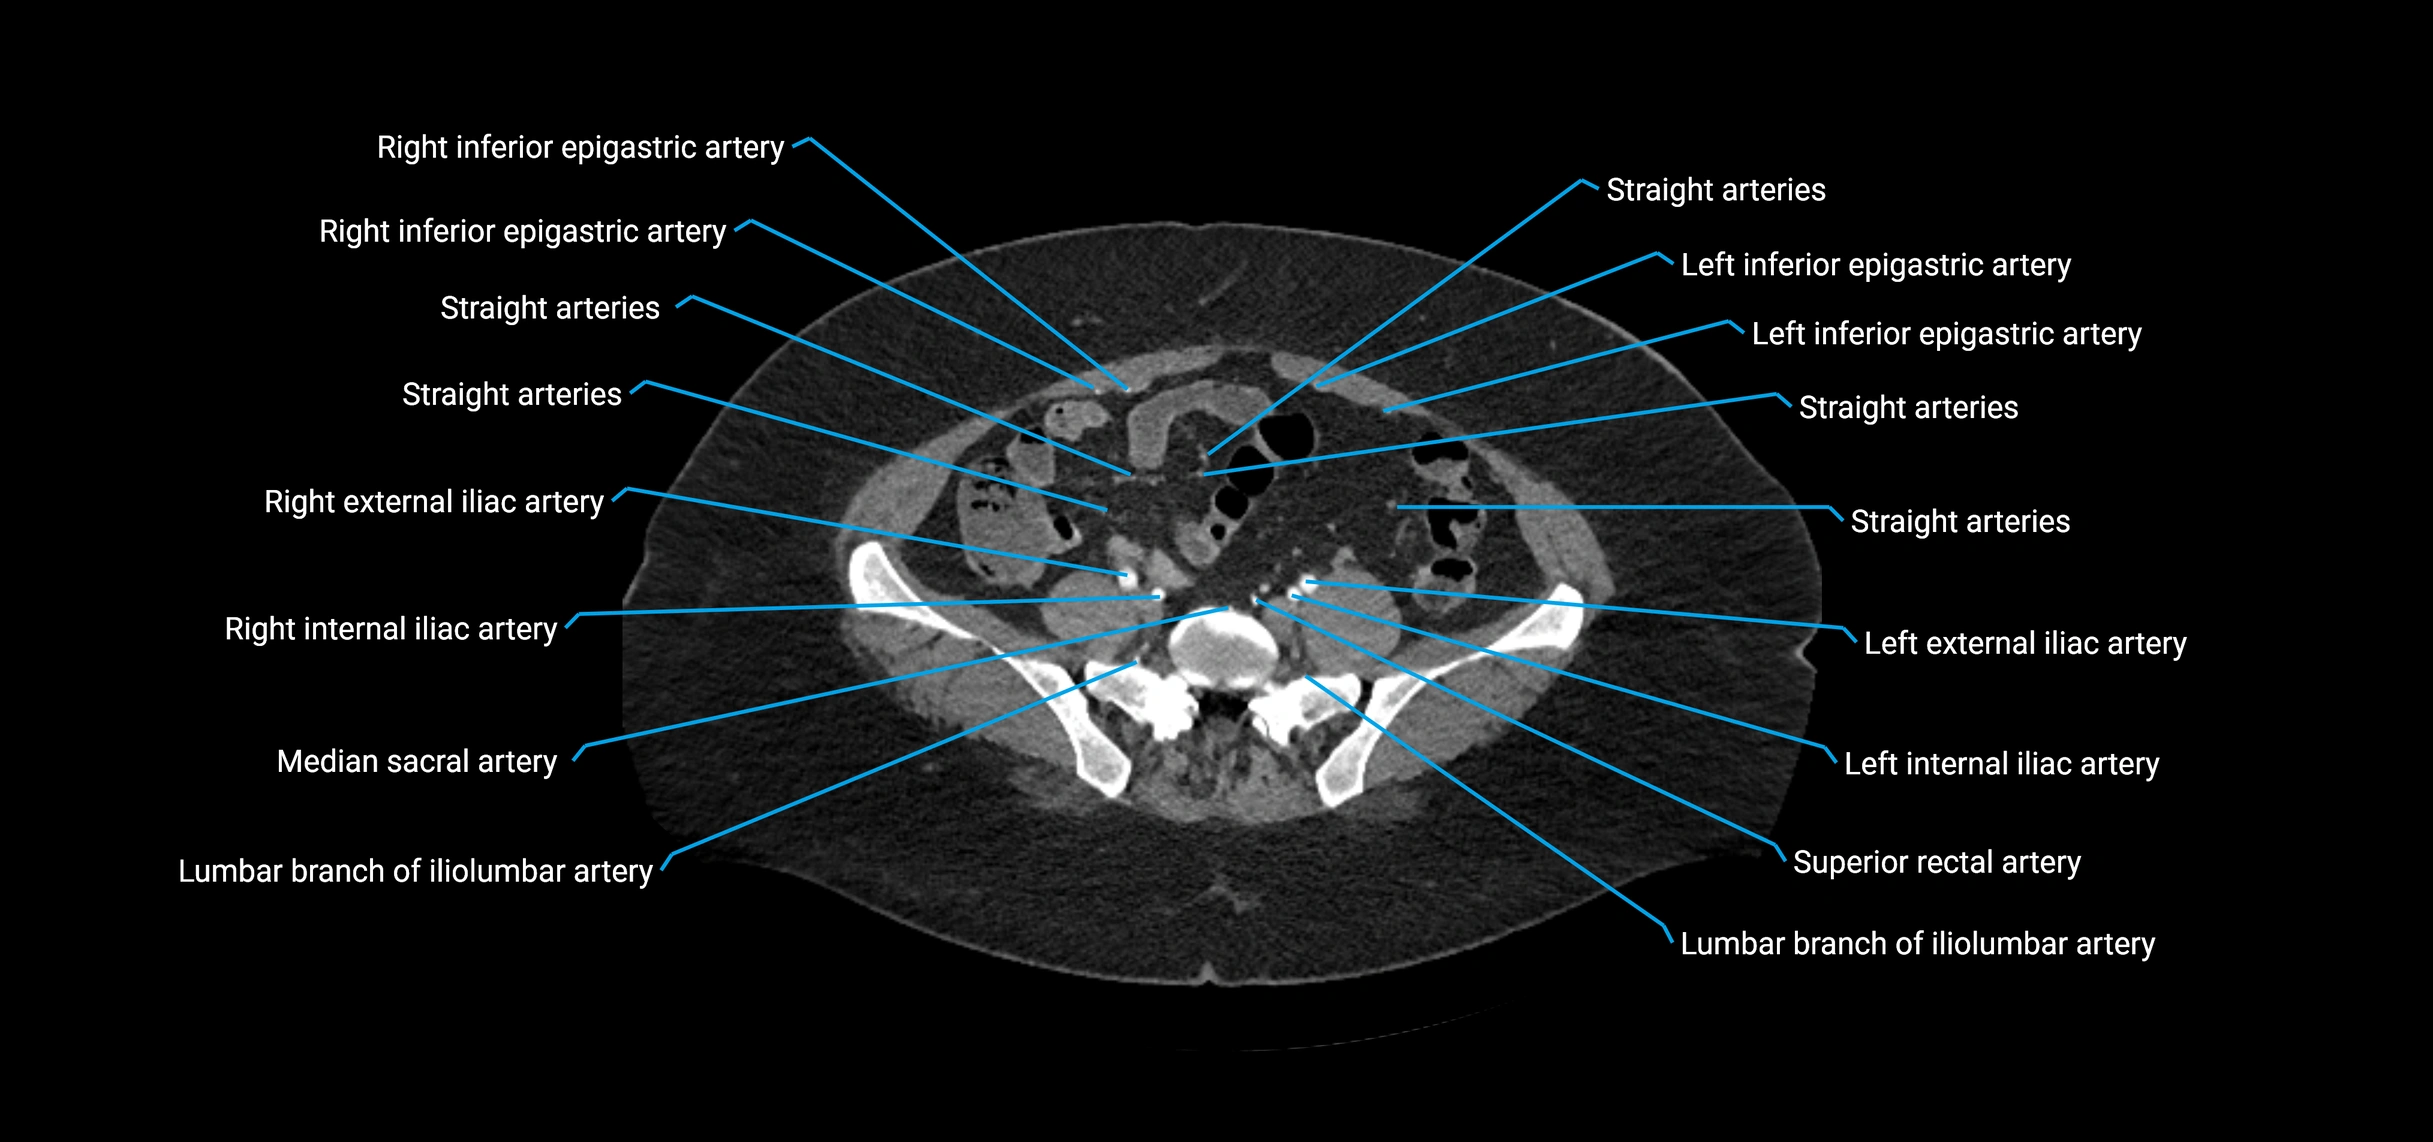

CT images

image